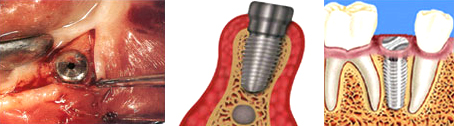

- 1차 수술

계획된 장치를 이용하여 적절한 위치에 임플란트를 심고 잇몸을 덮어주어 임플란트와 잇몸뼈 간의 결합을 유도합니다.

- 2차 수술

임플란트를 심어 놓으면 어느 정도의 치유기간이 필요하게 되는데 이는 임플란트와 주위골과의 결합이 잘 이루어지도록 기다리는 것입니다. 이 기간은 환자의 상태와 치아 상실부의 위치에 따라 차이가 있을 수 있으나 대체로 하악은 3-4개월, 상악은 6개월 정도가 지난 후 2차수술을 시행하게 됩니다. 2차수술은 간단히 점막을 다시 연 후 심어 놓은 임플란트위에 기둥 부분을 세우게 되며 이 기둥을 이용하여 보철물을 장착하게 됩니다.